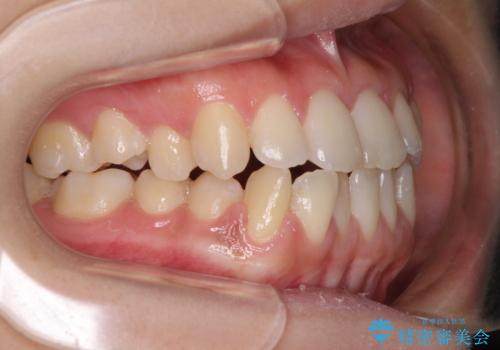

- 上下のデコボコと奥歯の咬みにくさを気にして来院された患者様です。

上顎骨の幅が下顎骨よりも小さく受け口傾向であったため、拡大装置により上顎骨の骨幅を広げて上下関係を改善し、その後インビザラインにて歯並びを整えることとしました。

下顎歯列は上顎歯列内に収まるように並んでいますが、上顎骨の幅が狭いと、下顎臼歯が全体的に舌側に傾斜した歯列となってしまいます。

舌側に傾斜した歯列は奥歯に力の負担がかかりやすく、歯磨きがしにくいなどの問題があるため、上顎骨拡大により舌側傾斜を改善することが可能となります。